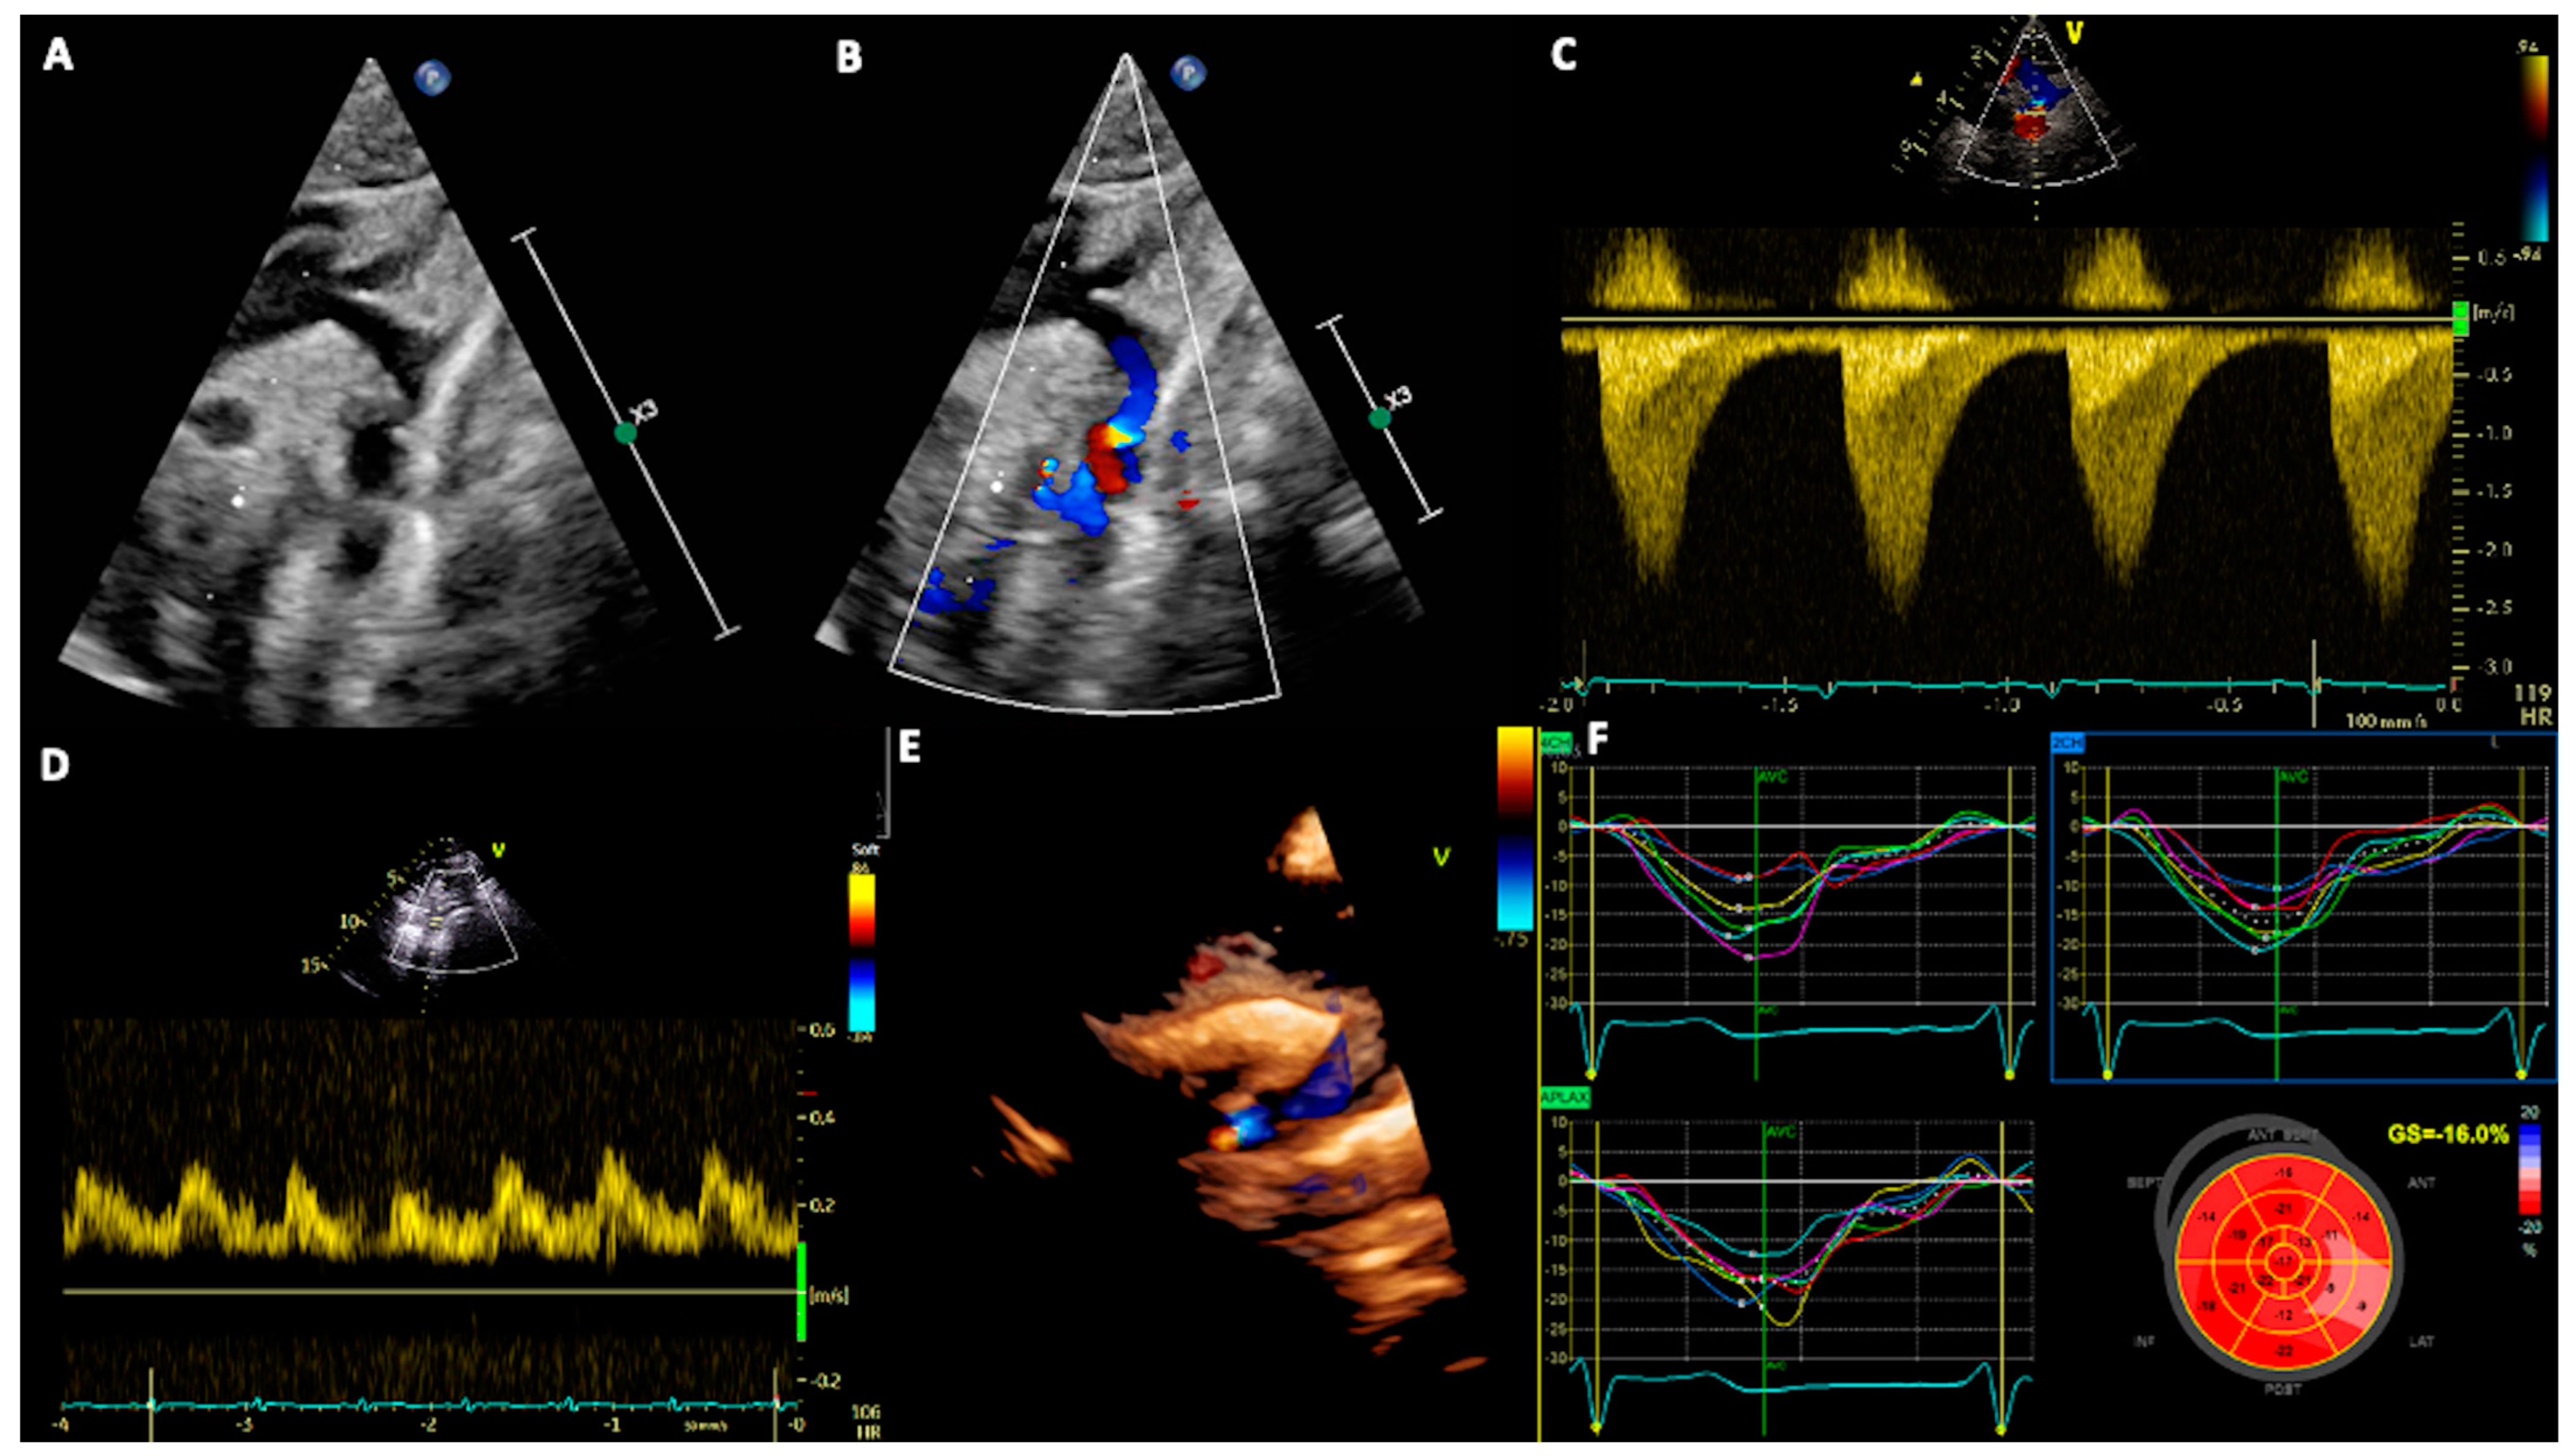

2. Echocardiography